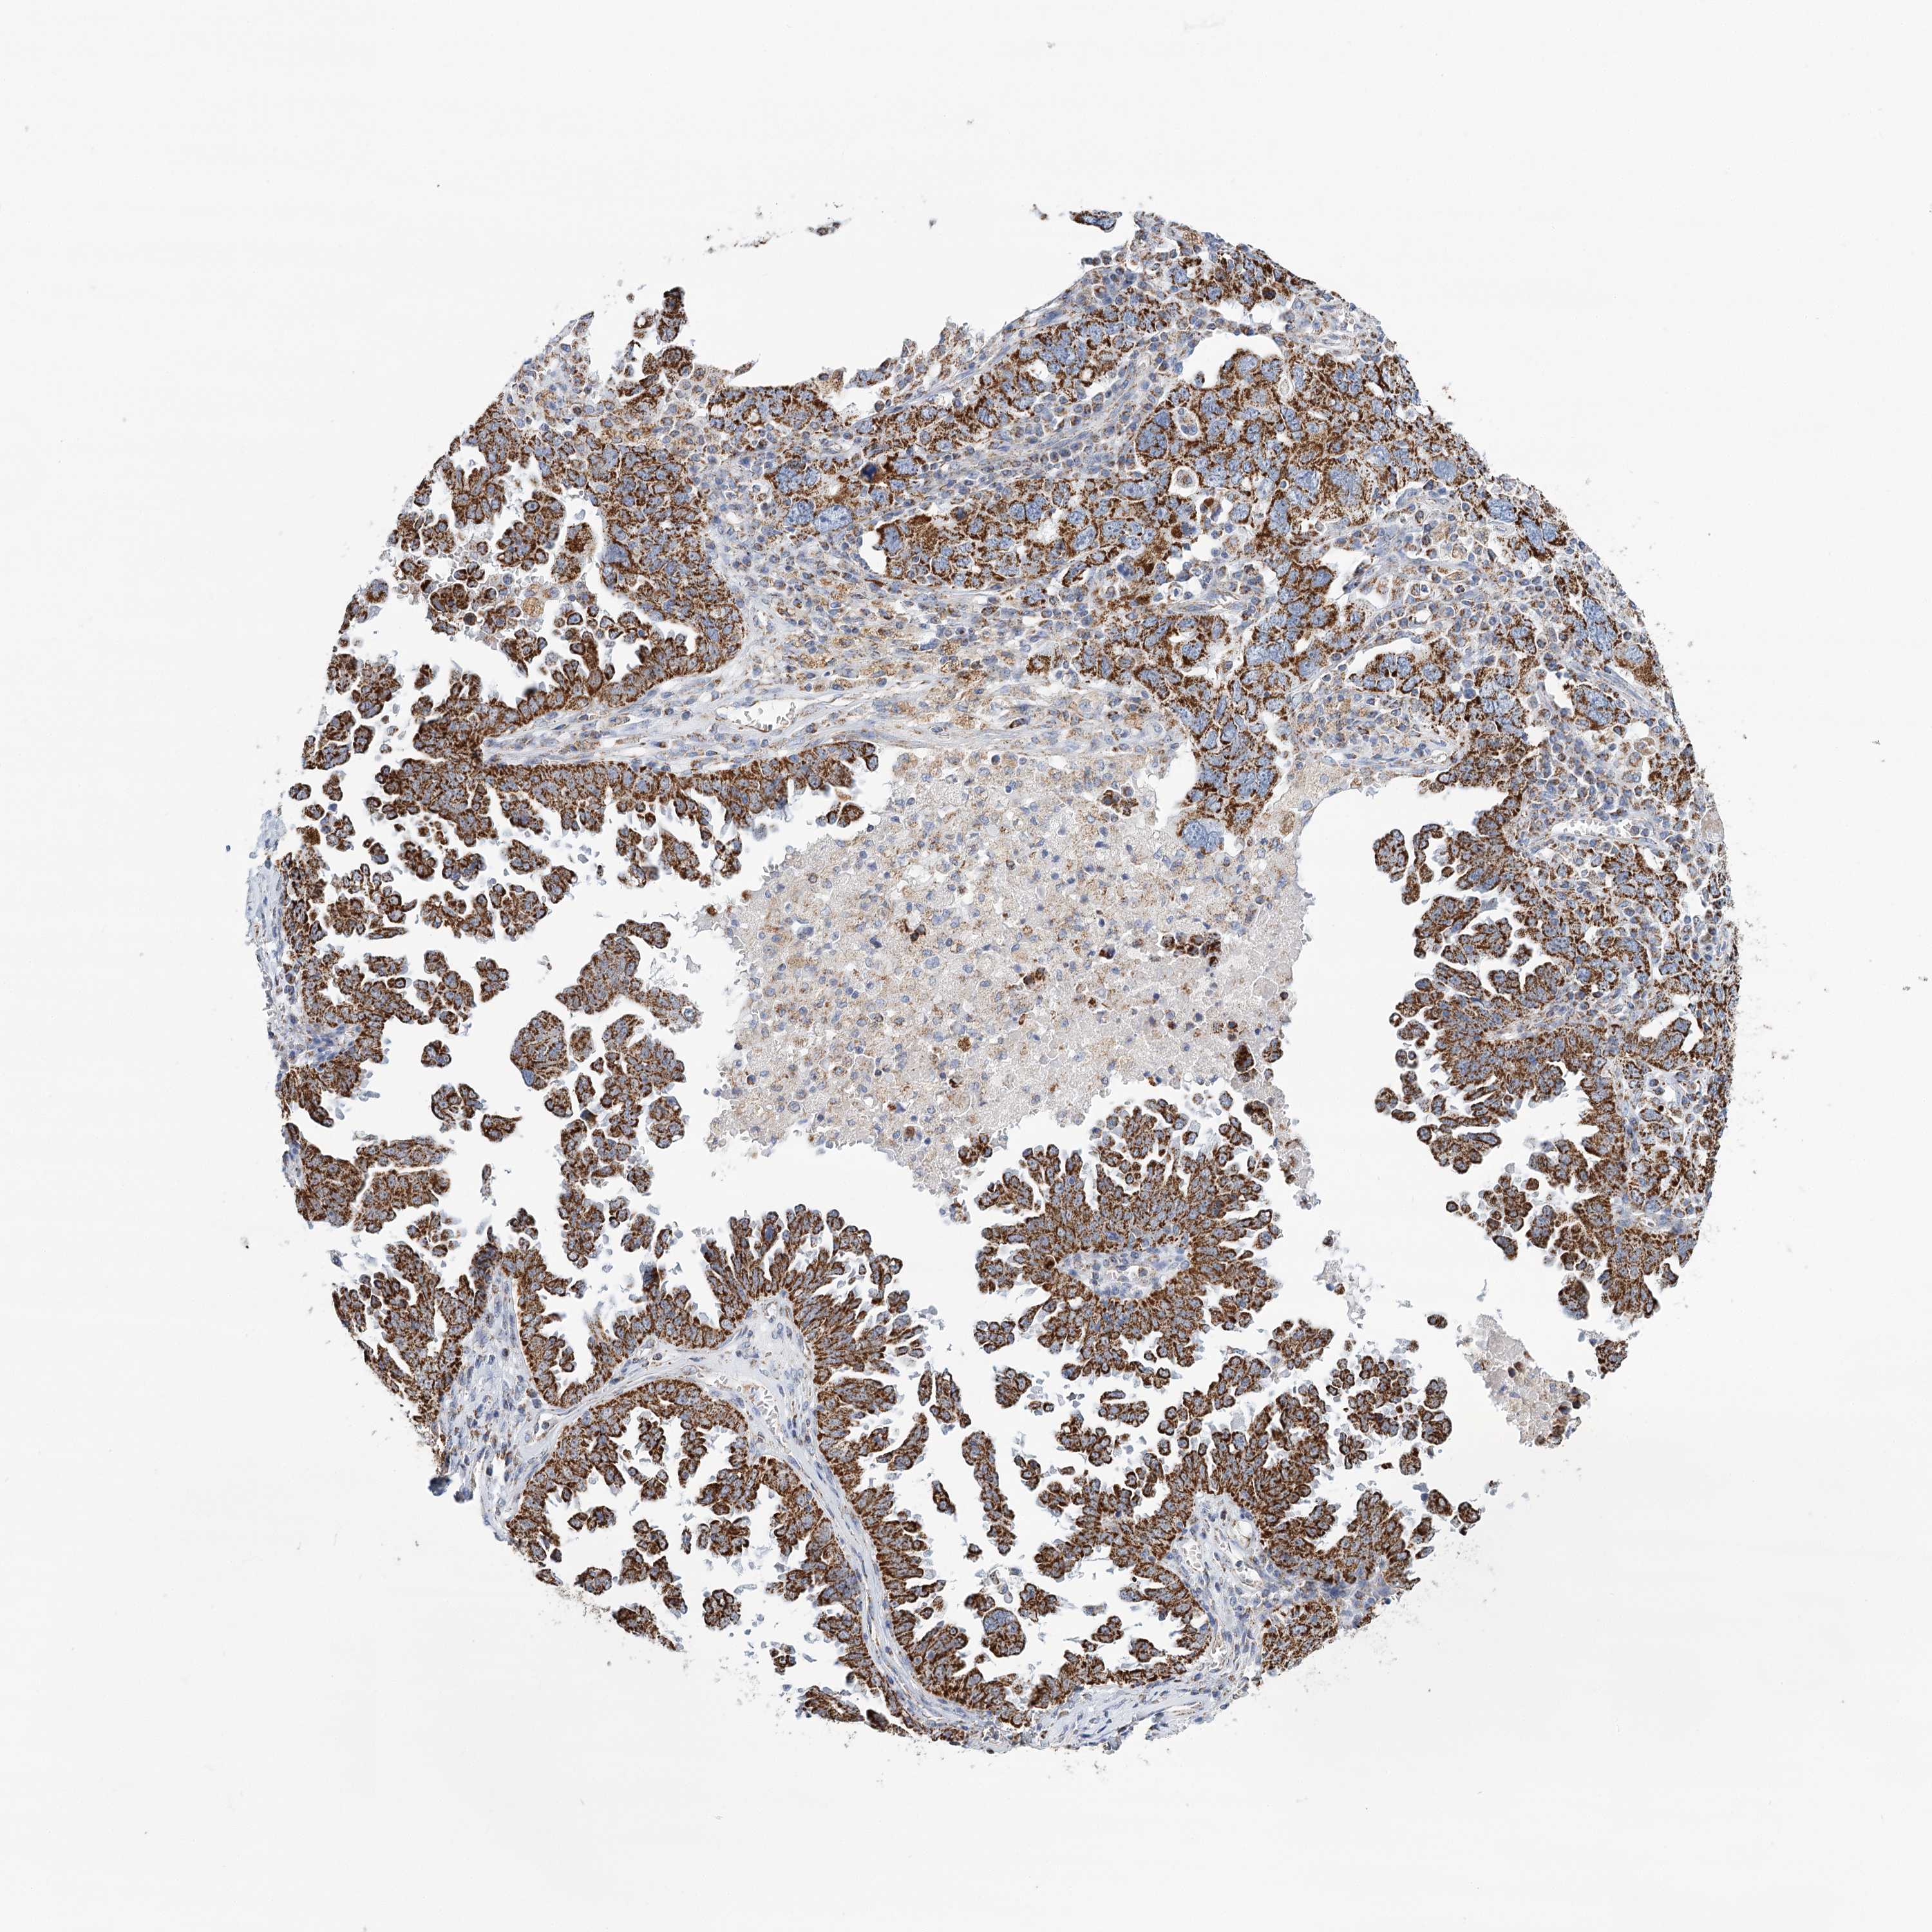

OVARIAN CANCER - Protein expressioni

A mouse-over function shows sample information and annotation data. Click on an image to view it in a full screen mode. Samples can be filtered based on level of antibody staining by selecting one or several of the following categories: high, medium, low and not detected. The assay and annotation is described here.

Note that samples used for immunohistochemistry by the Human Protein Atlas do not correspond to samples in the TCGA dataset.

Antibody stainingi

Antibody staining in the annotated cell types in the current human tissue is reported as not detected, low, medium, or high, based on conventional immunohistochemistry profiling in selected tissues. This score is based on the combination of the staining intensity and fraction of stained cells.

Each image is clickable and will lead to virtual microscopy that enables deeper exploration of all samples and also displays staining intensity scores, fraction scores and subcellular localization as well as patient and tissue information for each sample.

Antibody HPA032060

Antibody HPA032062

Antibody CAB034116

Staining

High

Medium

Low

Not detected

Intensity

Strong

Moderate

Weak

Negative

Quantity

>75%

75%-25%

<25%

None

Location

Nuclear

Cytoplasmic/membranous

Cytoplasmic/membranous,nuclear

Cystadenocarcinoma, serous, NOS

Carcinoma, endometroid

Cystadenocarcinoma, mucinous, NOS

Carcinoma, NOS